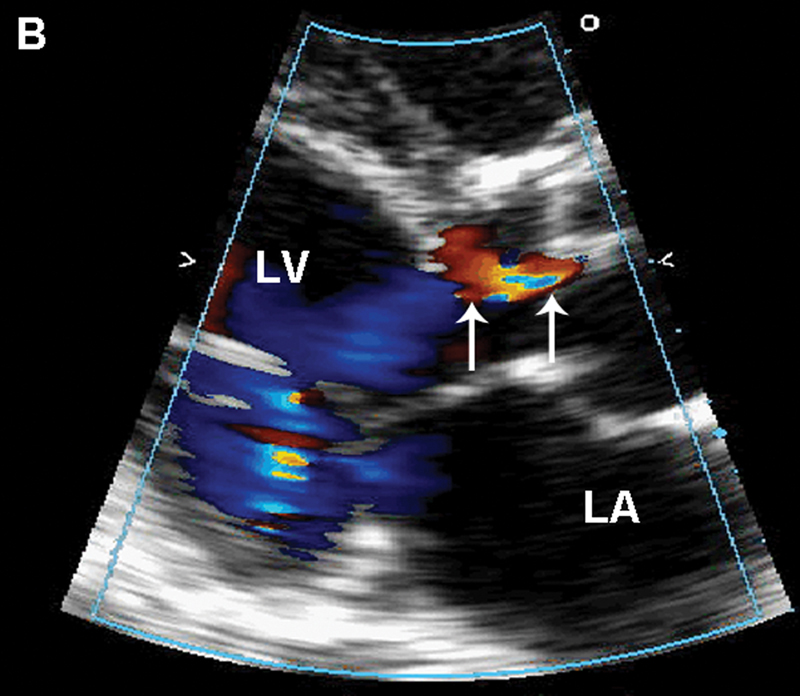

فحوصات تشخيصية لبعض امراض القلب والشرايين التاجية